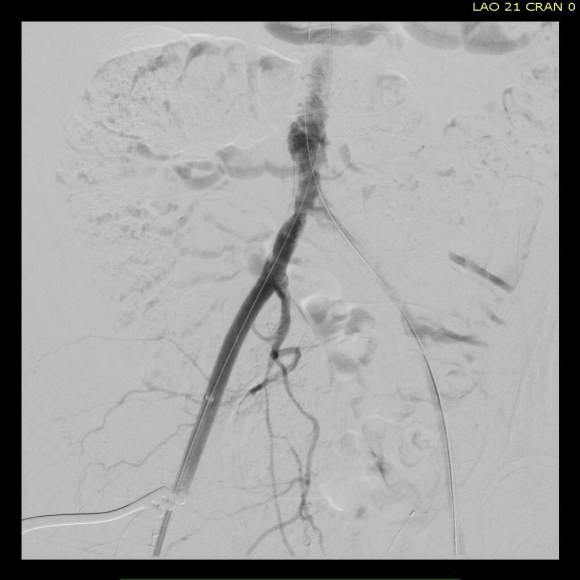

The patient was operated on in a hybrid endovascular OR suite. A right groin incision was made to expose the common femoral artery for endarterectomy and left common femoral access was achieved for angiographic access, but also to place a wire across the occlusion into the common femoral artery.

All actions on the external iliac artery plaque are done with an up-and-over wire, allowing for swift action in the instance that arterial perforation or rupture occur. This event is exceedingly rare when the operation is well planned. With this kind of access, an occlusive balloon or repairing stent graft can be rapidly delivered.

The common femoral endarterectomy is done from its distal most point and the Vollmer ring is used to mobilize the plaque. A Moll Ring Cutter (LeMaitre Vascular) is then used to cut the plaque.

The plaque is extracted and re-establishes patency of the EIA.

The plaque end point is typically treated with a stent -in this case, the common iliac plaque was also treated.